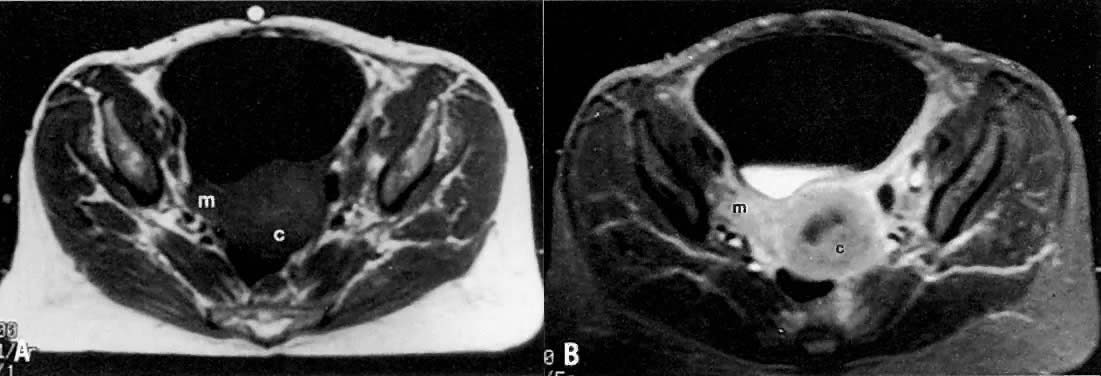

Fig. 16. A. Axial T1-weighted MRI of a stage IIB cervical carcinoma shows a mass ( m) extending from the cervical tumor ( c) in the right parametrium. B. Axial contrast-enhanced T1-weighted MRI shows enhancement of the cervical and parametrial mass after gadolinium bolus injection.(Mayr NA, Tali ET, Yuh WTC et al: Cervical cancer: Application of MR imaging in radiation therapy. Radiology 189:601, 1993)

Fig. 17. Recurrent cervical carcinoma with possible radiation changes in the bones and muscles. Sagittal ( A ), low-transverse ( B ), coronal ( C ), and high-transverse ( D) T1-weighted MRI of the pelvis show a large high-signal-intensity mass ( m) (density less than that of fat and more than that of muscle) superior and posterior to the bladder ( b ). Note thickening of the right lateral and superior bladder wall caused by tumor invasion ( arrows ). There is also spread of tumor to the pelvic sidewall ( arrowheads ). There is thickening and increased signal intensity to the right iliopsoas muscle ( ip) compared to the left. There is also evidence of increased signal intensity to the bone marrow of the sacrum and L5 in A. The muscle and bone changes are probably caused by radiation.

Peritumoral inflammatory reaction can mimic parametrial involvement, causing tumor overstaging on T2-weighted imaging.33 In addition to edema, factors including volume averaging, bowel peristalsis artifact, close proximity of structures, obliquity of planes, and anatomic variations may obliterate fat planes between the tumor and the surrounding organs, thus increasing the false-positive rate, especially in advanced disease.34 Gadolinium-enhanced T1-weighted MRI techniques do not seem to improve visualization of stromal invasion of cervical carcinoma, but do improve staging in advanced cases (see Fig. 16A and Fig. 16B).35 Recent studies have shown that gadolinium-enhanced dynamic MRI may be superior to T2-weighted MRI in the evaluation of stromal invasion.12 Fat suppression techniques may also better delineate the tumor margins (Fig. 14B) and detect bladder or rectal wall invasion.36 MRI using endorectal surface coils may also prove to be a promising technique because of improved resolution over conventional MRI techniques.37